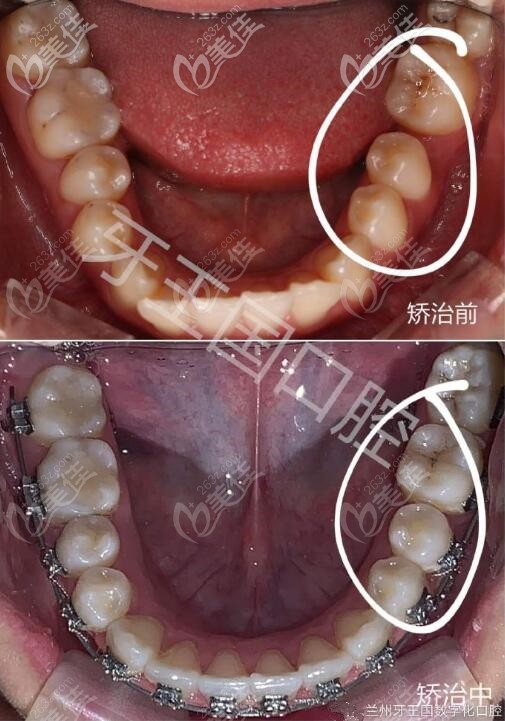

蘭州牙王國口腔診療范圍:牙齒矯正、種植牙、牙周炎、牙髓治療、鑲牙、牙齒美學修復兒童牙齒(窩溝封閉、涂氟等)。